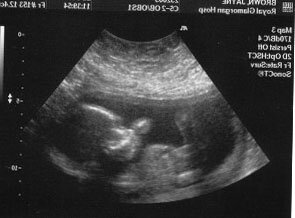

Беременность в 40 и 50 лет.. Врачи не считают это разумным

Если в 1970-х годах в Республике рождалось около тысячи женщин в год, то в последние годы их число возросло до трех тысяч. И даже пожилые женщины растут. Врачи не считают это очень разумным, так как осложнения беременности с возрастом увеличиваются. Мамы стареют. И они не являются исключением. Скорее всего, в последние два десятилетия Западная Европа оказалась в этом положении, где задержка материнства наблюдалась раньше.